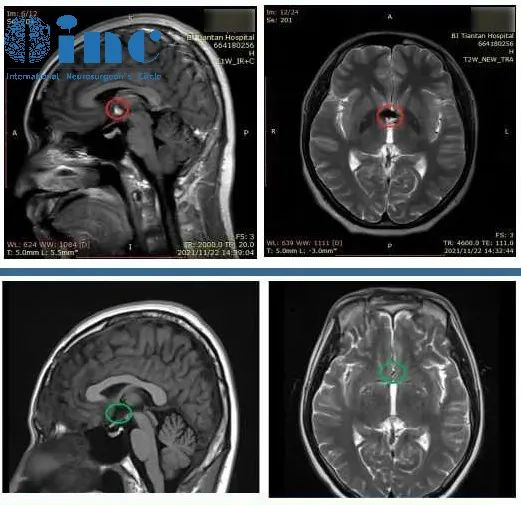

浩然术前术后MR影响对比全切病灶